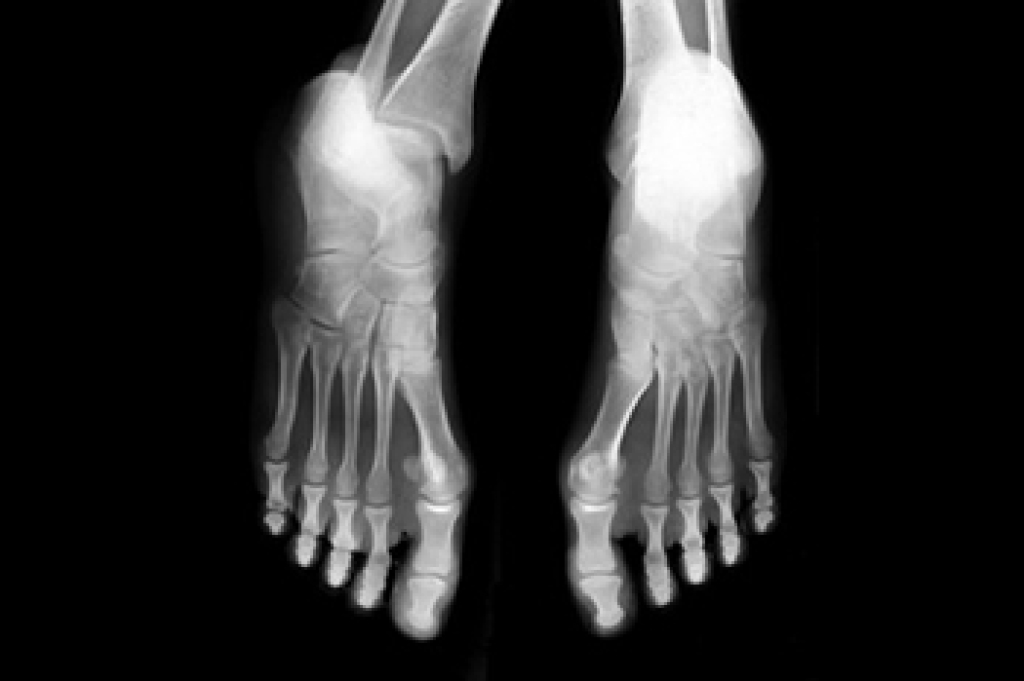

Broken Foot Causes, Symptoms, and Treatment

A broken foot is caused by one of the bones in the foot typically breaking when bended, crushed, or stretched beyond its natural capabilities. Usually the location of the fracture indicates how the break occurred, whether it was through an object, fall, or any other type of injury.

Those that suspect they have a broken foot shoot seek urgent medical attention where a medical professional could diagnose the severity.

Treatment for broken bones varies depending on the cause, severity and location. Some will require the use of splints, casts or crutches while others could even involve surgery to repair the broken bones. Personal care includes the use of ice and keeping the foot stabilized and elevated.